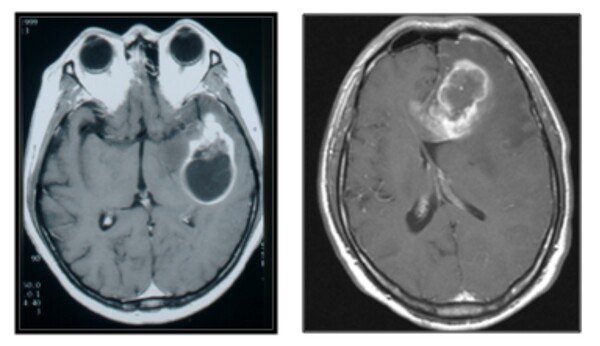

뇌종양 진단의 기본은 MRI 검사다. 이는 뇌종양이 의심될 때 뿐만 아니라, 수술 전후 종양의 상태 관찰을 위해 자주 사용된다. 검사에서는 종양 부위를 선명하게 확인할 수 있도록 정맥조영제를 투여한다.

뇌종양 진단 후에는 연령, 기저질환, 증상, 종양의 크기와 위치, 성장 속도를 검토해 치료 계획을 수립한다. 최종 진단은 수술로 종양을 제거한 후, 현미경으로 직접 세포를 관찰하고 종양세포에 대한 유전자검사까지 해 내리게 된다. 이를 통해 뇌종양으로 확진돼야 방사선치료나 항암화학요법 등 후속 치료를 진행할 수 있다.